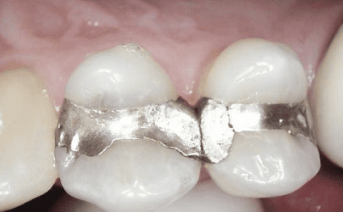

Our composite dental fillings in Atlanta, Georgia, not only fill in cavities, but can treat various cosmetic treatments by filling in teeth that have been damaged or demineralized. Schedule your treatment at Smiles of Atlanta with our dentist, to see if you need a composite dental filling from Dr. Ed Trizzino. Call 770-777-0808 today.